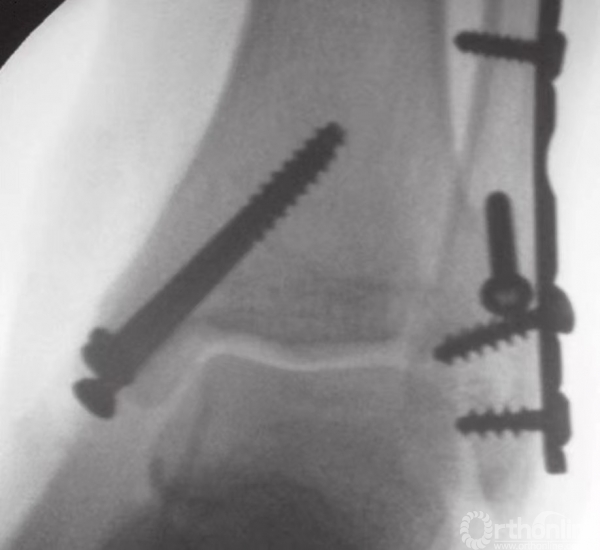

在钳的前方和后方,放置两枚较小的克氏针,并使之与骨折线垂直(图15)。注意要保证克氏针不刺穿踝关节(图16)。为防止刺穿关节,可将角度调至与水平方向约成30°。在克氏针上方和对侧皮质附近,使用管状钻钻孔。后嵌入4mm部分有螺纹的空心松质骨螺钉。

在骨折片尖部固定螺钉时,三角韧带表层可能会部分劈裂。再将另一枚螺钉以相同方式嵌入(图17),无需涉及对侧皮质。在大多数病例中,40或45mm长度规格的螺钉可以起到很好的固定作用。这些螺钉应相互平行,并在内踝骨折片上方铺开,以便更好地控制旋转(图18)。

图17 半螺纹松质骨空心钉最终固定骨折

图18 内踝固定完成

通过X线透视确认骨折复位和螺钉的固定(图19)。用可吸收缝线缝合较薄的皮下层后,再将皮肤缝合。